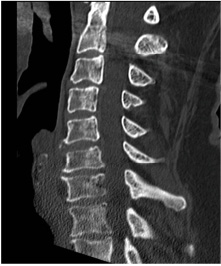

Pre-op CT demonstrates right C5-6 uncovertebral joint osteophyte causing foraminal stenosis but minimal facet arthrosis.